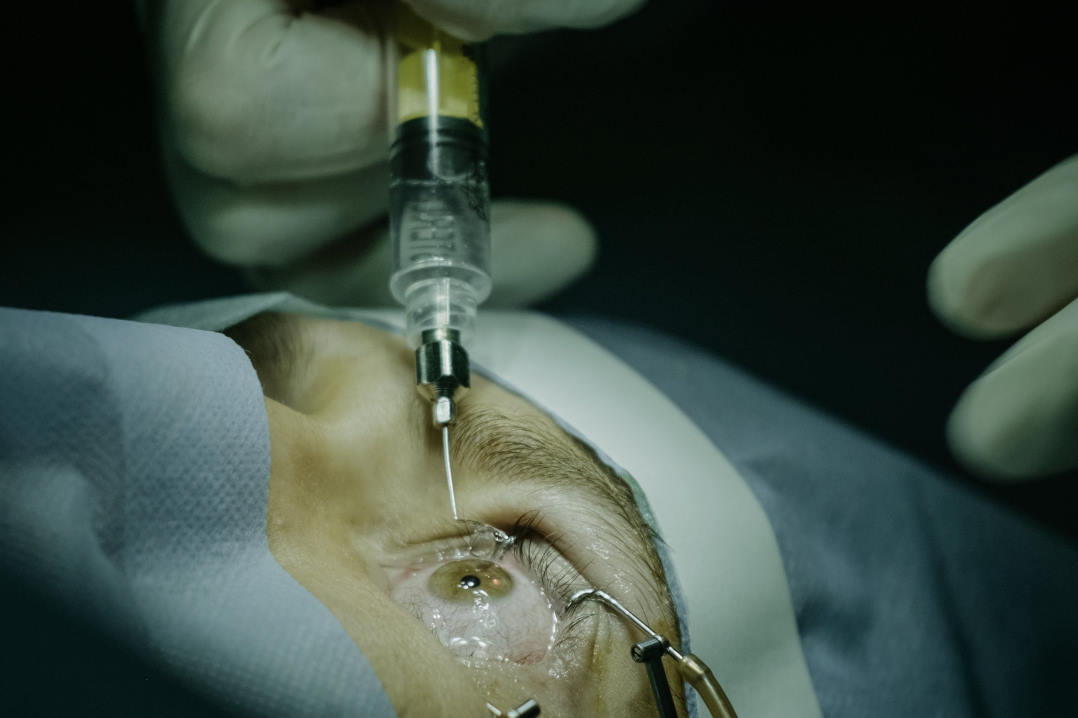

Dead in the eye

In true James Bond style, researchers from Warsaw University of Technology have trained artificial intelligence (AI) algorithms to tell the difference between the irises of dead and live people to prevent a dead person’s eyeball from being used to circumvent security measures. The team used a database of iris scans from dead bodies and living people to train the algorithm, resulting in dead irises being detected with 100% accuracy, and giving the probability of live irises being misclassified at just 1%.

However, this level of accuracy is only reached after the person has been dead for 16 hours or more, said the study’s authors in MIT Technology Review. “Samples collected briefly after death can fail to provide post-mortem changes pronounced enough to serve as cues for liveness detection… giving these gruesome hackers a window of opportunity since freshly plucked eyeballs should work a treat.”